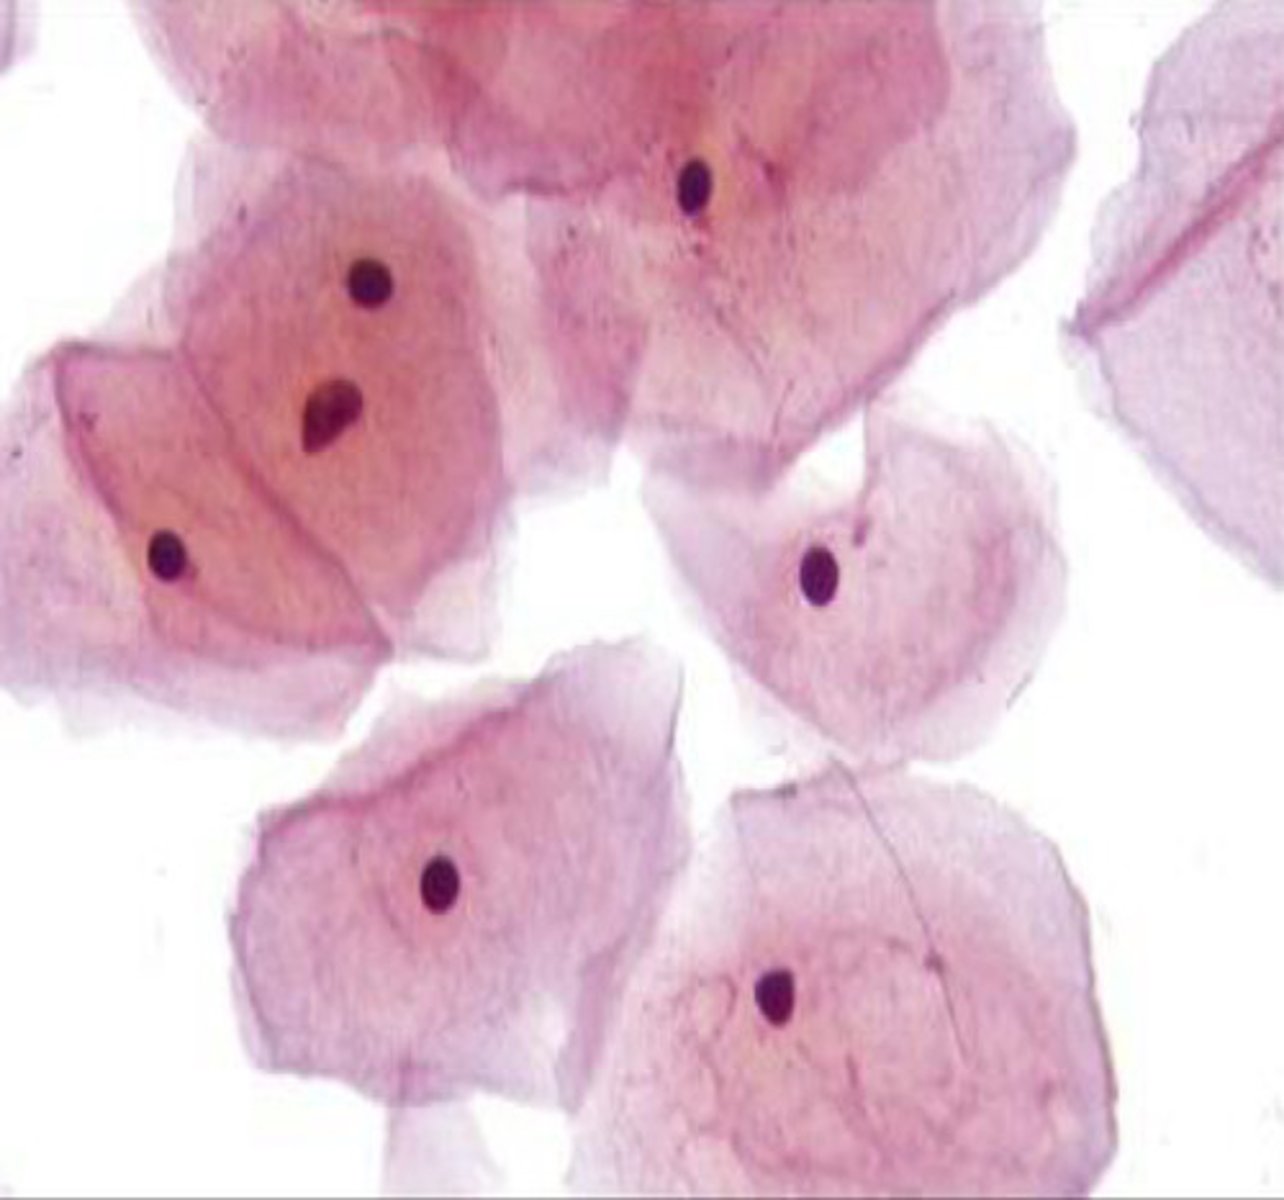

squamous epithelial cell

urine

-large, flat, irregularly shaped

-central nucleus, large amount of cytoplasm

squamous epithelial cell

urine